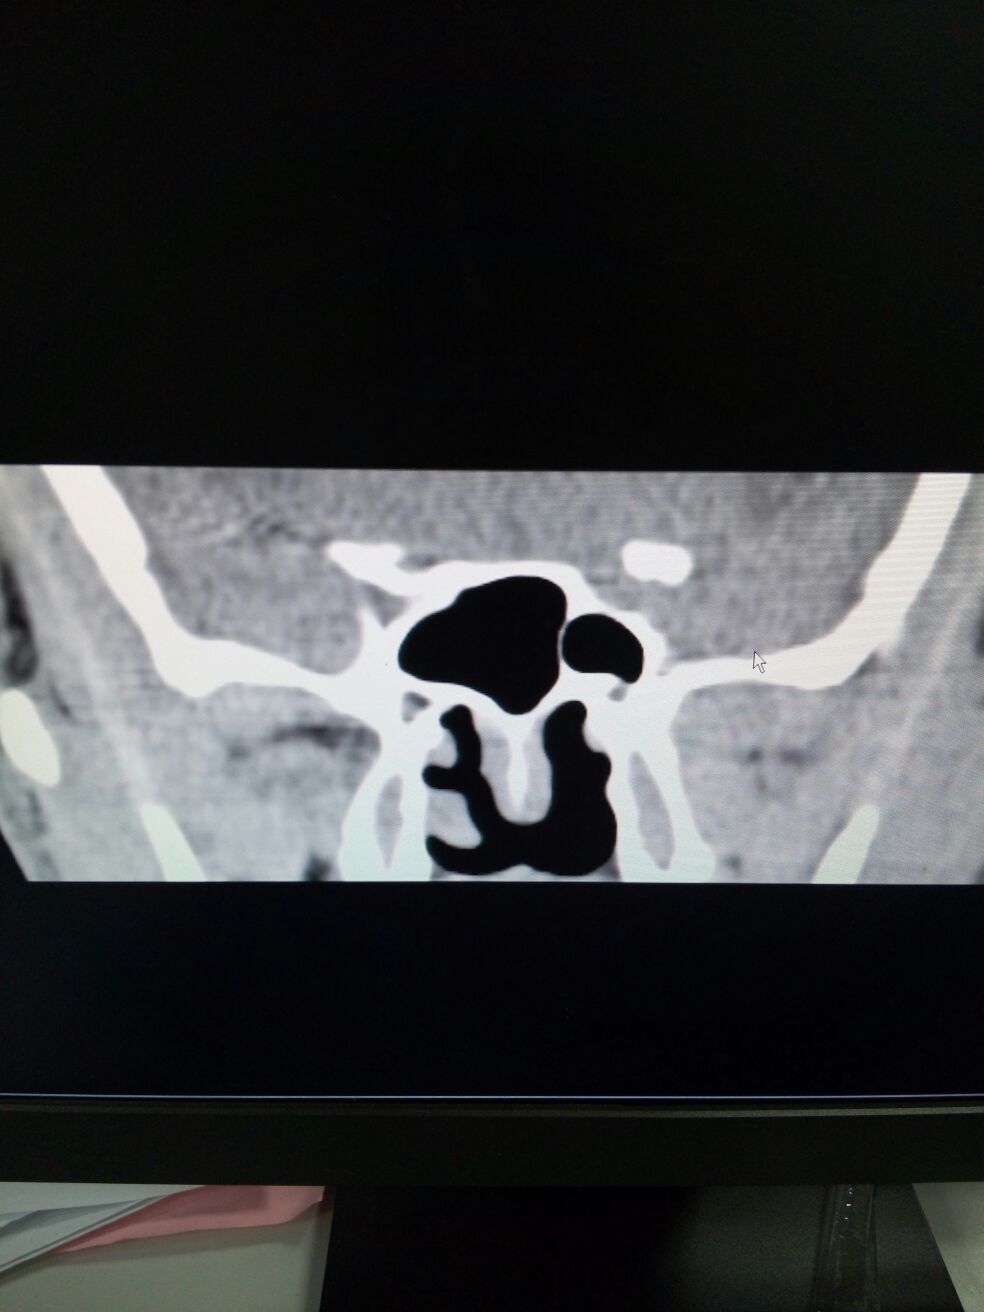

男,32岁。头痛2年,加重3月。查体:肢端肥大样貌,余无特殊。头颅CT诊断:垂体瘤。病理结果示垂体腺瘤。临床诊断:垂体生长激素腺瘤。

补充矢状位和病理结果。男,32岁。头痛2年,加重3月。查体:肢端肥大样貌,余无特殊。头颅CT诊断:垂体瘤。病理结果示垂体腺瘤。临床诊断:垂体生长激素腺瘤。